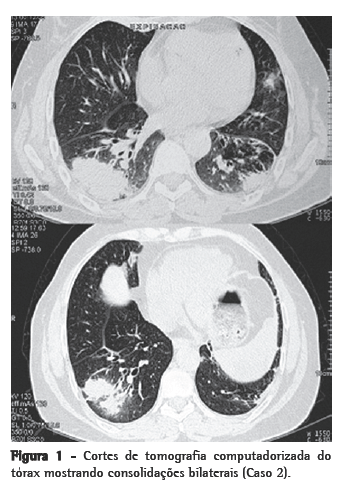

Paciente feminina, 58 anos, não-tabagista, iniciou com tosse, emagrecimento moderado, cansaço e dores articulares. Tinha antecedentes de asma na infância, com reinício após os 40 anos, que relacionava ao contato com tintas e solventes no trabalho. Uso inalatório diário de formoterol e budesonida 12/400 µg, com bom controle dos sintomas. A radiografia e tomografia de tórax mostravam consolidações bilaterais e algumas bronquiectasias em lobos inferiores (Figura 1). Os exames laboratoriais revelaram: hematócrito, 41,1%; hemoglobina, 13,7 g/dL; leucócitos, 8.970/mm3, com linfopenia (1.076 linfócitos); plaquetas, 285.000; FAN reagente (1:160), com padrão nuclear pontilhado; VHS, 56 mm; e proteína C reativa, 27,60 mg/L. Na época, suspeitou-se granulomatose de Wegener, pela presença no soro de antineutrophil cytoplasmic antibody (ANCA, anticorpo anticitoplasma de neutrófilos). Não foi notado comprometimento das vias aéreas superiores. Foi iniciada terapêutica com ciclofosfamida. Ainda no primeiro mês, foi notado um aumento do gânglio cervical anterior esquerdo. À biópsia do linfonodo, foi identificada linfadenite crônica granulomatosa com extensa necrose não-caseosa (Figura 2). A pesquisa de BAAR foi negativa. Pela suspeita de tuberculose, recebeu o esquema RHZ por 6 meses, apresentando melhora clínica. Entretanto, nos dois anos seguintes, persistiu com cansaço, dores articulares, episódios pneumônicos circunscritos e lesão oral na base da língua nos últimos 6 meses, fazendo uso temporário de corticosteróides sistêmicos e antibióticos (5 a 6 vezes, por 10 a 14 dias). Com o incremento desses sintomas, procurou novamente atendimento. Exames laboratoriais mostraram FAN 1:80, padrão nuclear homogêneo; anti-DNA não-reagente, linfopenia e VHS de 65 mm. A revisão do diagnóstico anatomopatológico confirmou linfadenite crônica granulomatosa com necrose e numerosos histiócitos vacuolados, presença de células gigantes tipo Langerhans e pesquisa de BAAR e de fungos negativas. Adicionalmente, foi realizado painel de imunohistoquímica: CD68 (KP-1) positivo (histiócitos xantomatosos) e mieloperoxidase negativa, sugestivo de DKF (Figura 2). Considerou-se então estar a paciente apresentando evolução combinada da doença (não diagnosticada há dois anos) com lúpus eritematoso sistêmico (LES), passando a ficar controlada pelo acréscimo de azatioprina oral (100 mg/dia) e prednisona (40 mg/dia) progressivamente descontinuada, com melhora clínica e dos exames laboratoriais e tomográficos, em 1 mês.